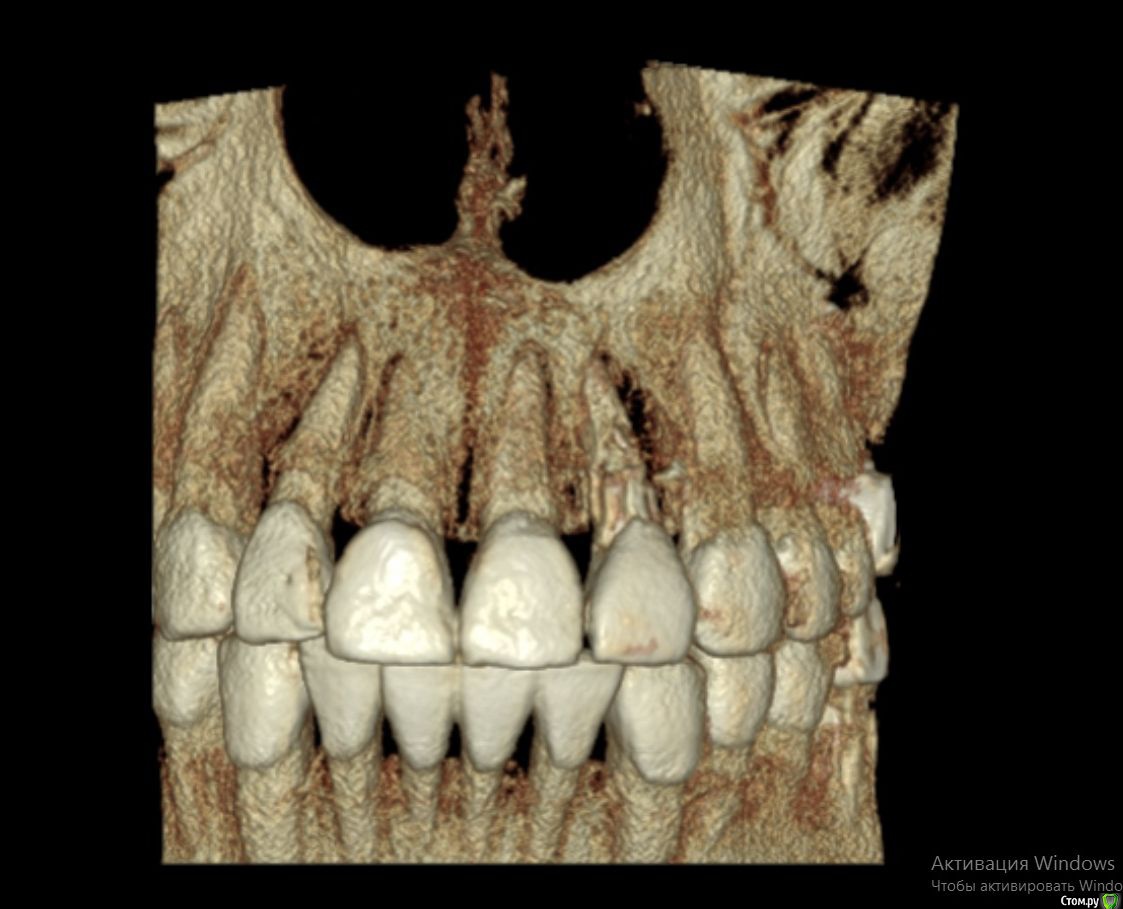

Bier Опубликовано 21 апреля, 2017 Поделиться Опубликовано 21 апреля, 2017 3д реконструкция нам не подходит. Хотя по ней все довольно печально выглядит.покажите скриншоты срезов. Ссылка на комментарий

колесников Опубликовано 21 апреля, 2017 Поделиться Опубликовано 21 апреля, 2017 Резецировать там нечего,во время эндодонтического лечения произошла перфорация стенки корня зуба,вокруг этого участка очаг деструкции костной ткани. Это не лечится.По выставленной вами картинке объём деструкции не понятен. Решить возможность одномоментной имплантации и тем более немедленной нагрузки может только ваш лечащий доктор ,по результатам кт и в соответствии со своим опытом. Ссылка на комментарий